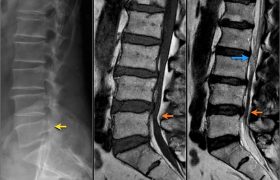

Причины стеноза позвоночного канала

Хотя есть некоторое пространство между спинным мозгом и краем позвоночного канала, есть немало различных путей, как это пространство может уменьшиться. Кости и связки окружают позвоночный канал. Это трубка, которая не может расширяться, если спинной мозг и нервы требуют больше места. Если что-то начинает сужать позвоночный канал, риск раздражения и травмы спинного мозга или нервов увеличивается.Некоторые из причин, которые...